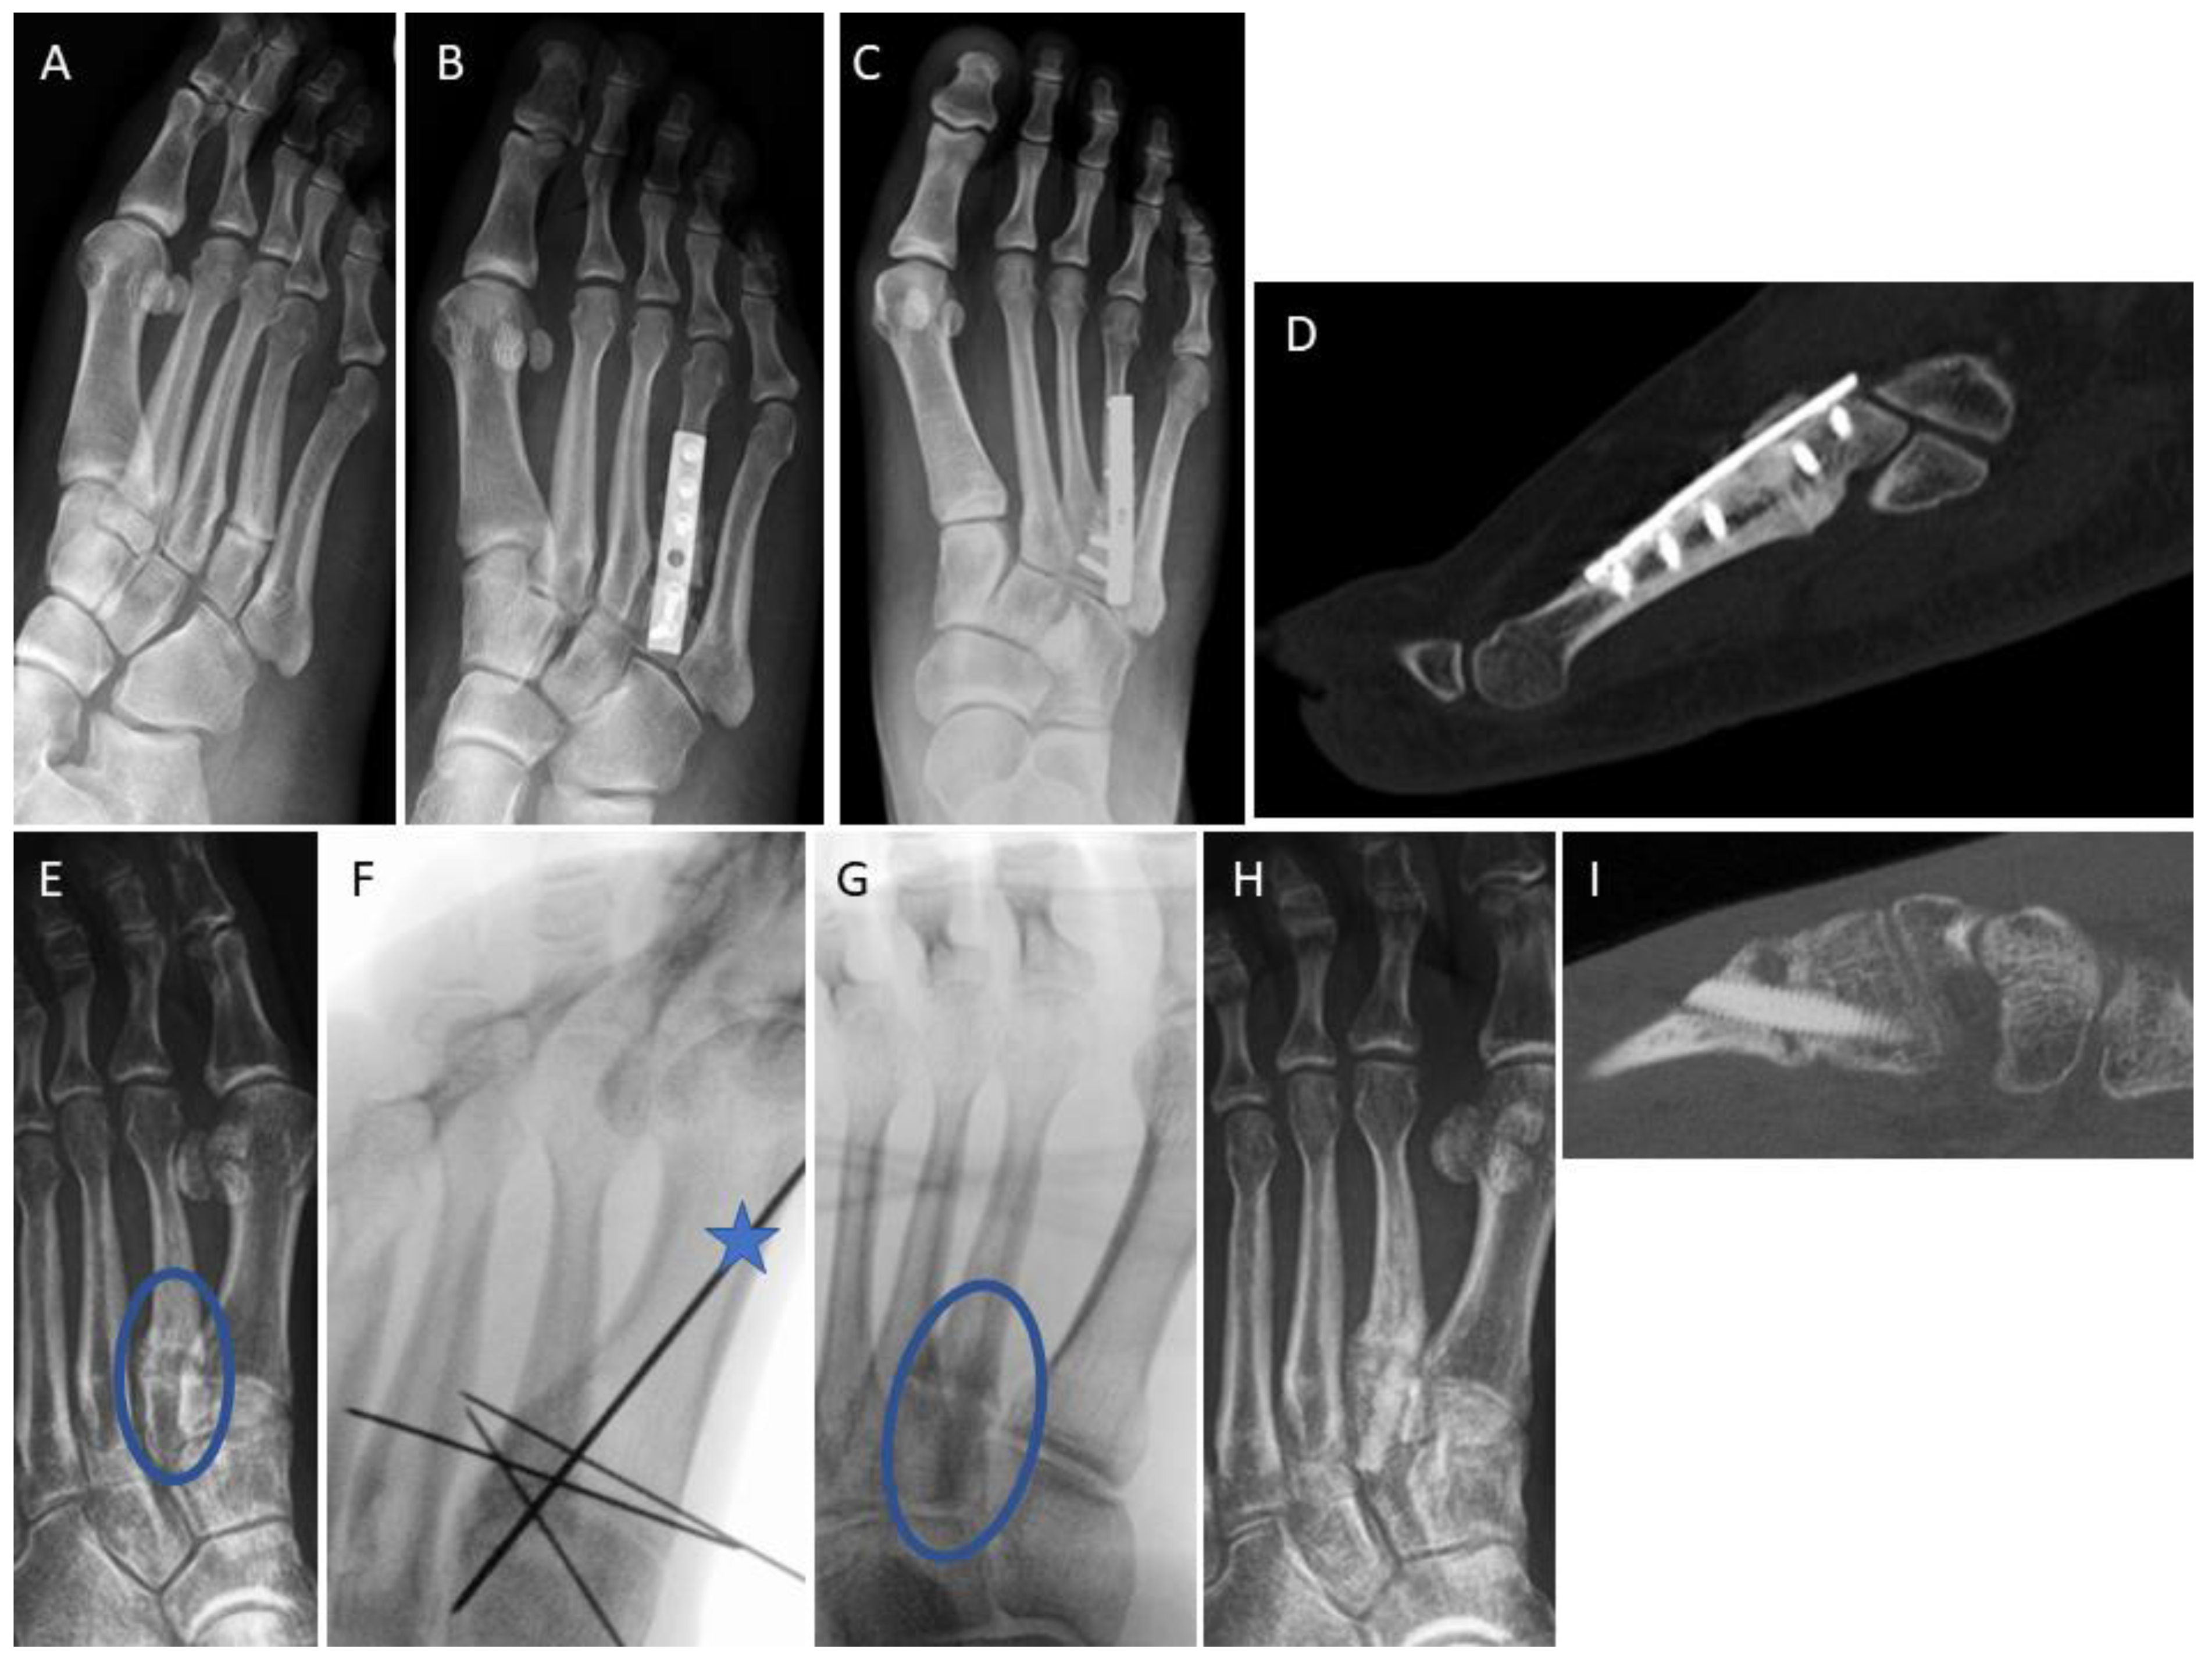

3.4. Examples for Bone Healing

3.6. Radiological Findings of Interest